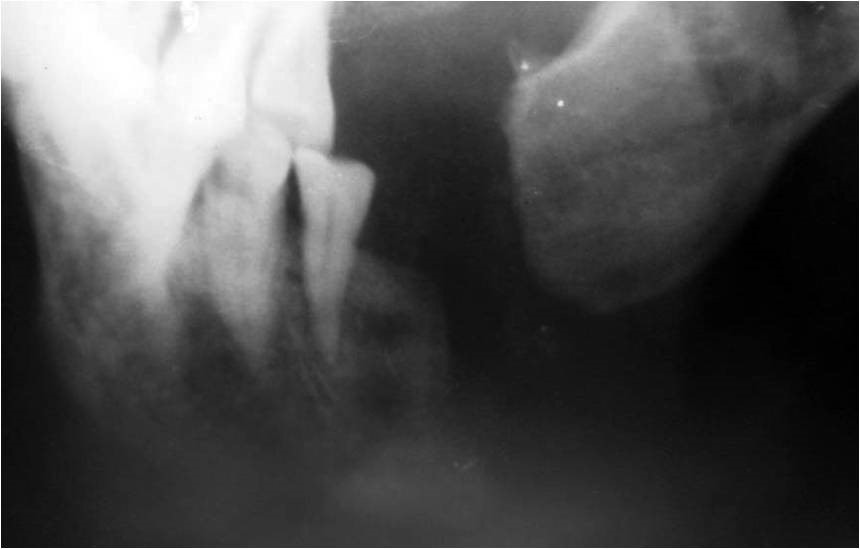

2304. На рентгенограмме у пациента с переломом нижней челюсти наблюдается осложнение в виде